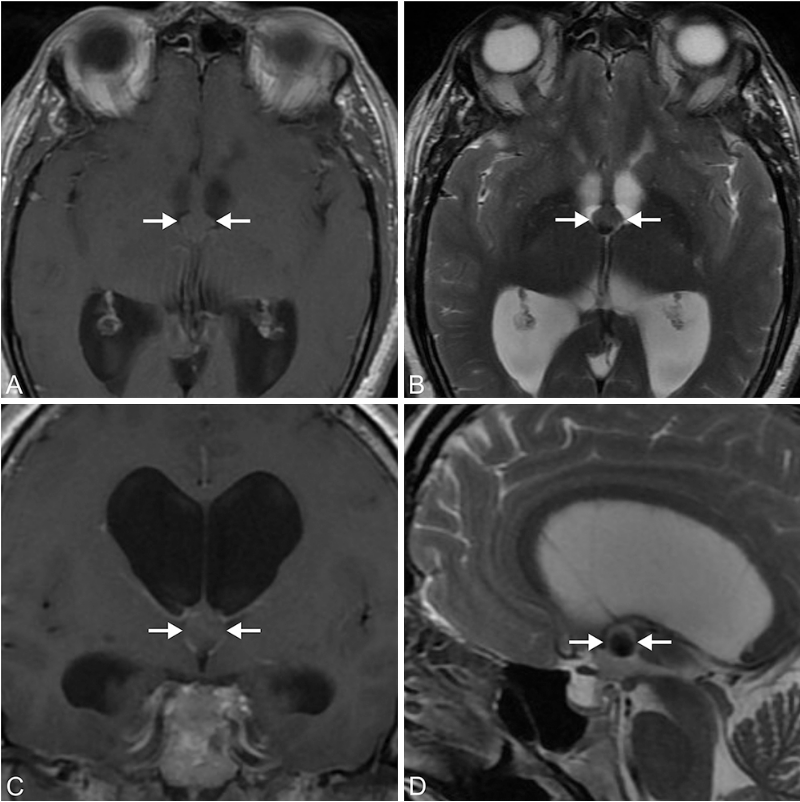

术前磁共振成像显示胶样囊肿,导致双侧脑室积水。

术后3年获取的 T1 加权(A 为轴位)和 T2 加权(B 为轴位;C 为冠状位;D 为矢状位)磁共振图像显示无囊肿复发。